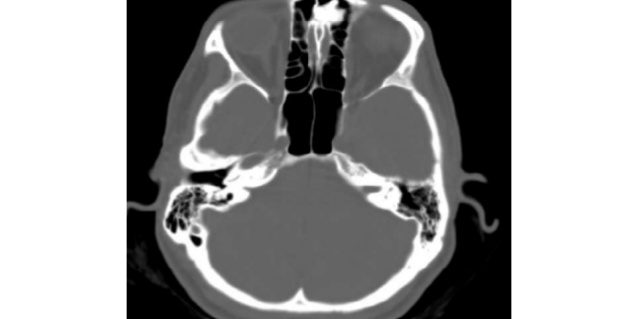

Fig.2 – Prania e osteomes frontoethmoidale ne CT. Fig.3 Ro rafi pas heqjes te osteomes.

Pacientia 48 vjec diagnostikohet pas nje egzaminimi Ro-grafik te sinuseve paranasale pasi paraqiste nje dhimbje te vazhduar te kokes dhe prej disa vitesh trajtohej me medikamente te ndryshem pa efikasitet. Per saktesim diagnoze u be CT i kokes dhe u pa qarte madhesia dhe shtrirja e osteomes e cila e merrte orgjinen nga septum intrasinusal i sinusit frontal dhe shtrihej brenda kufijve te sinusit. Interventi kirurgjikal per heqien e saj u realizua me incision fronto-orbital[Lothrop].